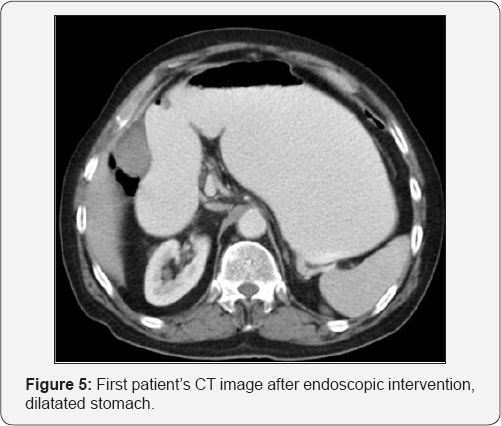

In the urgent endoscopic examination of the patient, the stomach was visualized to be full, showing an obstruction along with phytobezoar at the outlet (Figure 3). The phytobezoar was broken down with endoscopic hook and its transition to the duodenum was visualized (Figure 4). However, as a result of distention finding in the patient whose vomiting complaint have restarted during the follow-up, abdominal CT was repeated and phytobezoar causing obstruction at the ileum was visualized (Figure 5 & 6). An emergent operation was planned for the patient, and prior to the operation, prophylactic 1 g of cephazolin and 500 mg of metronidazole were intravenously administered and the patient was taken into emergent operation and underwent enterotomy after diagnostic laparotomy, and phytobezoar was removed (Figure 7 & 8). The patient who did not have any complaint or complication postoperatively, was discharged.

Clinically, patients present with obstruction findings, such as abdominal distention, abdominal pain, nausea and vomiting [1]. Direct x-rays, the firstline diagnostic techniques, may provide visualization of ileus findings, such as air-fluid levelings, as well as free air in cases of perforation. However, they are not sufficient to reveal the etiologic cause [1]. The abdominal CT is an important diagnostic tool with a sensitivity rate of 90% and a specificity rate of 96%. Well-demarcated intra-luminal mass with air bubbles, along with dilated intestinal loops and collapsed loops following mass can be visualized in CT [7]. In our first case, a gastric phytobezoar that migrated after the endoscopy was visualized in the jejunal loops in the tomographic images (Figures 1-4). Whereas in our second case, bezoar causing obstruction in the ileum was visualized (Figure 5).